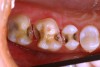

Figure 7 demonstrates a quadrant of old amalgam restorations present on a 32-year-old patient. Clinically, teeth Nos. 2 and 3 tested positive for cuspal fracture. Teeth Nos. 3 through 5 had radiographic evidence of recurrent decay. Each of these teeth had numerous treatment options. A case could be made for all four posterior teeth to be restored with crowns, and this certainly was one treatment option. However, with this young patient every effort was made to minimize the loss of tooth structure while still providing the functional restoration required to provide protection of the tooth and return each tooth to proper health and function while meeting the patient’s esthetic requests.

The gold onlay was cemented to place using a self-etching resin cement (Maxcem Elite™, Kerr Corporation). Self-etch cements have demonstrated less postoperative sensitivity, are less technique-sensitive, and will bond to the tooth structure and the restorations.22 The indirect composite inlay and onlay were cemented to place using a total-etch technique and a dual-cure resin cement (NX3 Nexus® Third Generation, Kerr Corporation) using a rubber dam. The final result is functionally durable and esthetic (Figure 10).

Figure 10  The 2-week postoperative view of the restored quadrant.

Figure 10